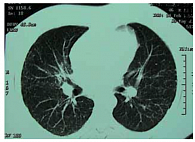

Рис. 1. Клинический случай 1. Диссеминация в сочетании с интерстициальными изменениями при рентгеновской компьютерной томографии (РКТ) органов грудной клетки у больного саркоидозом

У больного А., 49 лет, служащего, при очередном флюорографическом обследовании была обнаружена двусторонняя диссеминация. У больного не было жалоб. При объективном исследовании были пропальпированы надключичные лимфатические узлы. Дыхание было везикулярным, хрипы не выслушивались. Изменений кожи, поражений глаз и суставов не было обнаружено. Больной был направлен в противотуберкулезный диспансер. Реакция Манту была положительной – папула 16 мм (2 туберкулиновые единицы (ТЕ) туберкулина очищенного (ППД-Л)), кислотоустойчивые микобактерии (КУМ) в мокроте выявлены не были. Был предположен диссеминированный туберкулез легких и назначен комплексный противотуберкулезный препарат Майрин-П (изониазид + пиразинамид + рифампицин + этамбутол). Спустя 2 месяца клинический эффект от лечения отсутствовал, и после фтизиатрической комиссии противотуберкулезная терапия была отменена, выставлен диагноз «саркоидоз», пациент направлен к пульмонологу. Повторно проведенная туберкулиновая проба была отрицательной, КУМ обнаружены не были. Функция внешнего дыхания не страдала (форсированная жизненная емкость легких (ФЖЕЛ) составила 125%, объем форсированного выдоха за 1 секунду (ОФВ₁) – 127% от должных величин), диффузионная способность легких по окиси углерода (DLco) – 125% от должной. В клиническом анализе крови: СОЭ 8 мм/час, лейкоцитов 7 × 10⁹/л, лимфоцитов в лейкоформуле – 31%. Ультразвуковое исследование (УЗИ) органов брюшной полости патологии не выявило. При рентгеновской компьютерной томографии (РКТ) органов грудной клетки имела место диссеминация в сочетании с интерстициальными изменениями (рис. 1). При тщательном осмотре были выявлены ограниченные изменения кожи головы (рис. 2) и тела. Была проведена биопсия кожи, которая обнаружила хроническое гранулематозное воспаление саркоидного типа. Был выставлен окончательный клинический диагноз: «саркоидоз внутригрудных лимфатических узлов и легких, периферических лимфатических узлов и кожи». Учитывая большой объем поражения и полиорганность, была запланирована терапия системными стероидами, от которой больной отказался. В качестве альтернативы был назначен пентоксифиллин по 0,2 г 3 раза в день и витамин E по 200 мг 2 раза в день. Спустя 8 месяцев этой терапии больной чувствовал себя удовлетворительно, но кожные изменения оставались неизменными. При проведении РКТ в динамике было отмечено ухудшение картины – увеличение количества очагов в легких, множественные очаги в плевре (рис. 3). Функция дыхания оставалась в пределах нормы, но динамика была отрицательной (ФЖЕЛ 103%, ОФВ₁ 105% от должных, DLco 117% от должной). Был назначен преднизолон в суточной дозе 30 мг (утро – день) и витамин Е. Спустя 6 месяцев терапии кожные проявления прошли, согласно РКТ-картине была достигнута положительная динамика (рис. 4). К этому моменту суточная доза преднизолона оставалась 10 мг. Однако стероидная терапия сопровождалась такими явлениями, как увеличение массы тела (с 79 кг до 94 кг), снижение остроты зрения, разрушение зубов. Через 3 месяца лечение преднизолоном (курс 9 месяцев) было завершено, но в это время появились слабость, изменения на коже головы, свидетельствовавшие о начале обострения после отмены преднизолона. Пациенту было предложено провести терапию метотрексатом, но он отказался, и ему был начат повторный курс стероидной терапии.